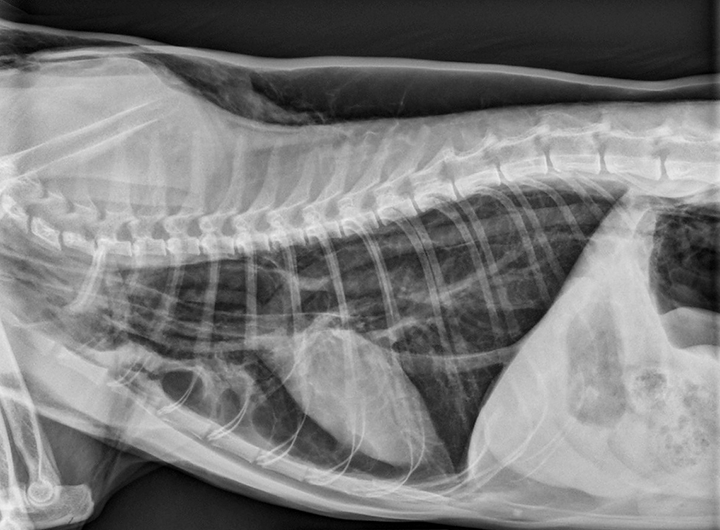

From www.shutterstock.com

Xray Cat Injured Trachea Stock Photo 673814119 Shutterstock Tracheal Rupture Cat Cuffed tubes have been associated with tracheal trauma in cats including tracheal. Understanding the signs, symptoms, and treatment options for this issue can go a long way in managing it effectively. This injury can be avoided with. Most tracheal tears in cats are iatrogenic and occur with cuf overinflation, as seen with dental procedures. Review clinical data on tracheal rupture. Tracheal Rupture Cat.

From www.researchgate.net

Lateral cervical radiographic view of a cat with a tracheal rupture Tracheal Rupture Cat This injury can be avoided with. Based on interviews with liability insurers, the author suggests five techniques to avoid tracheal tears in cats: Review clinical data on tracheal rupture associated with recent endotracheal intubation in cats and evaluate medical and surgical treatments for. Understanding the signs, symptoms, and treatment options for this issue can go a long way in managing. Tracheal Rupture Cat.